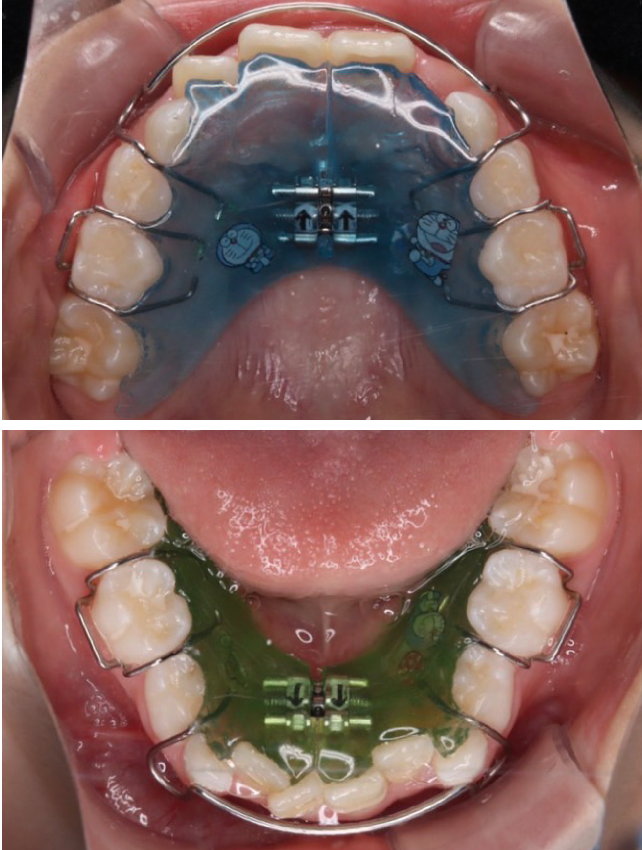

お子さまの

モチベーション維持

を徹底サポート

口腔内写真をアプリで共有しています!毎月写真を保護者・お子さまに共有し、治っている経過を可視化することで、お子さまの装着に対するモチベーションにつなげます!

1期治療で使用する装置

拡大床

- 機能

- 横に広げるための装置

- 期間

- 6か月~10か月程度

成長期のお子さまの顎をゆっくりと広げる矯正装置です。顎の成長を正しい方向へ導くことで、歯がきれいに並ぶための土台を整えます。歯を無理に動かすのではなく、顎の成長を活かした治療のため、痛みが少なく、お子さまへの負担が比較的軽いのが特徴です。

拡大床は、多くの場合1期治療の中心となる装置で、将来的な本格矯正の必要性を減らすことにもつながります。 -

当院の症例

CASE